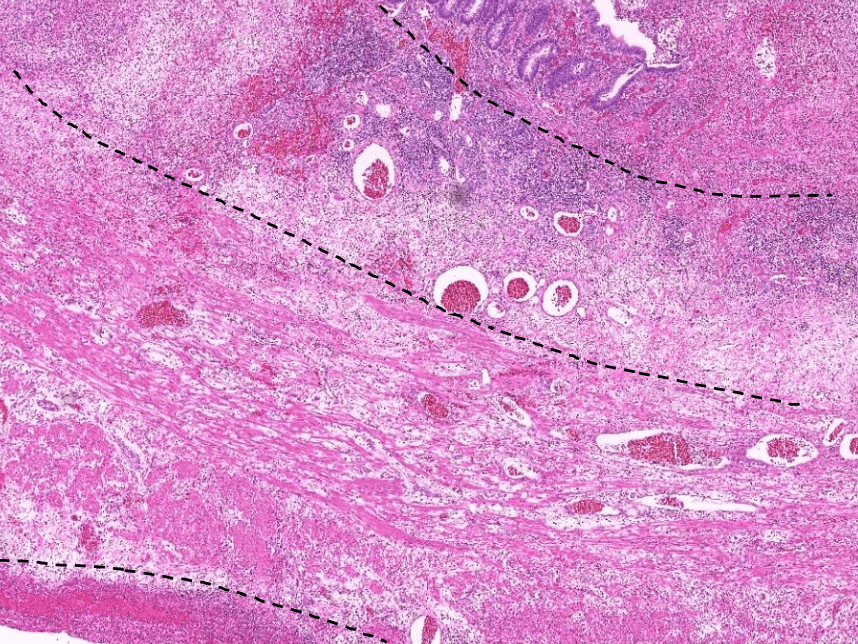

lung adenocarcinoma

colon cancer

endometrial cancer